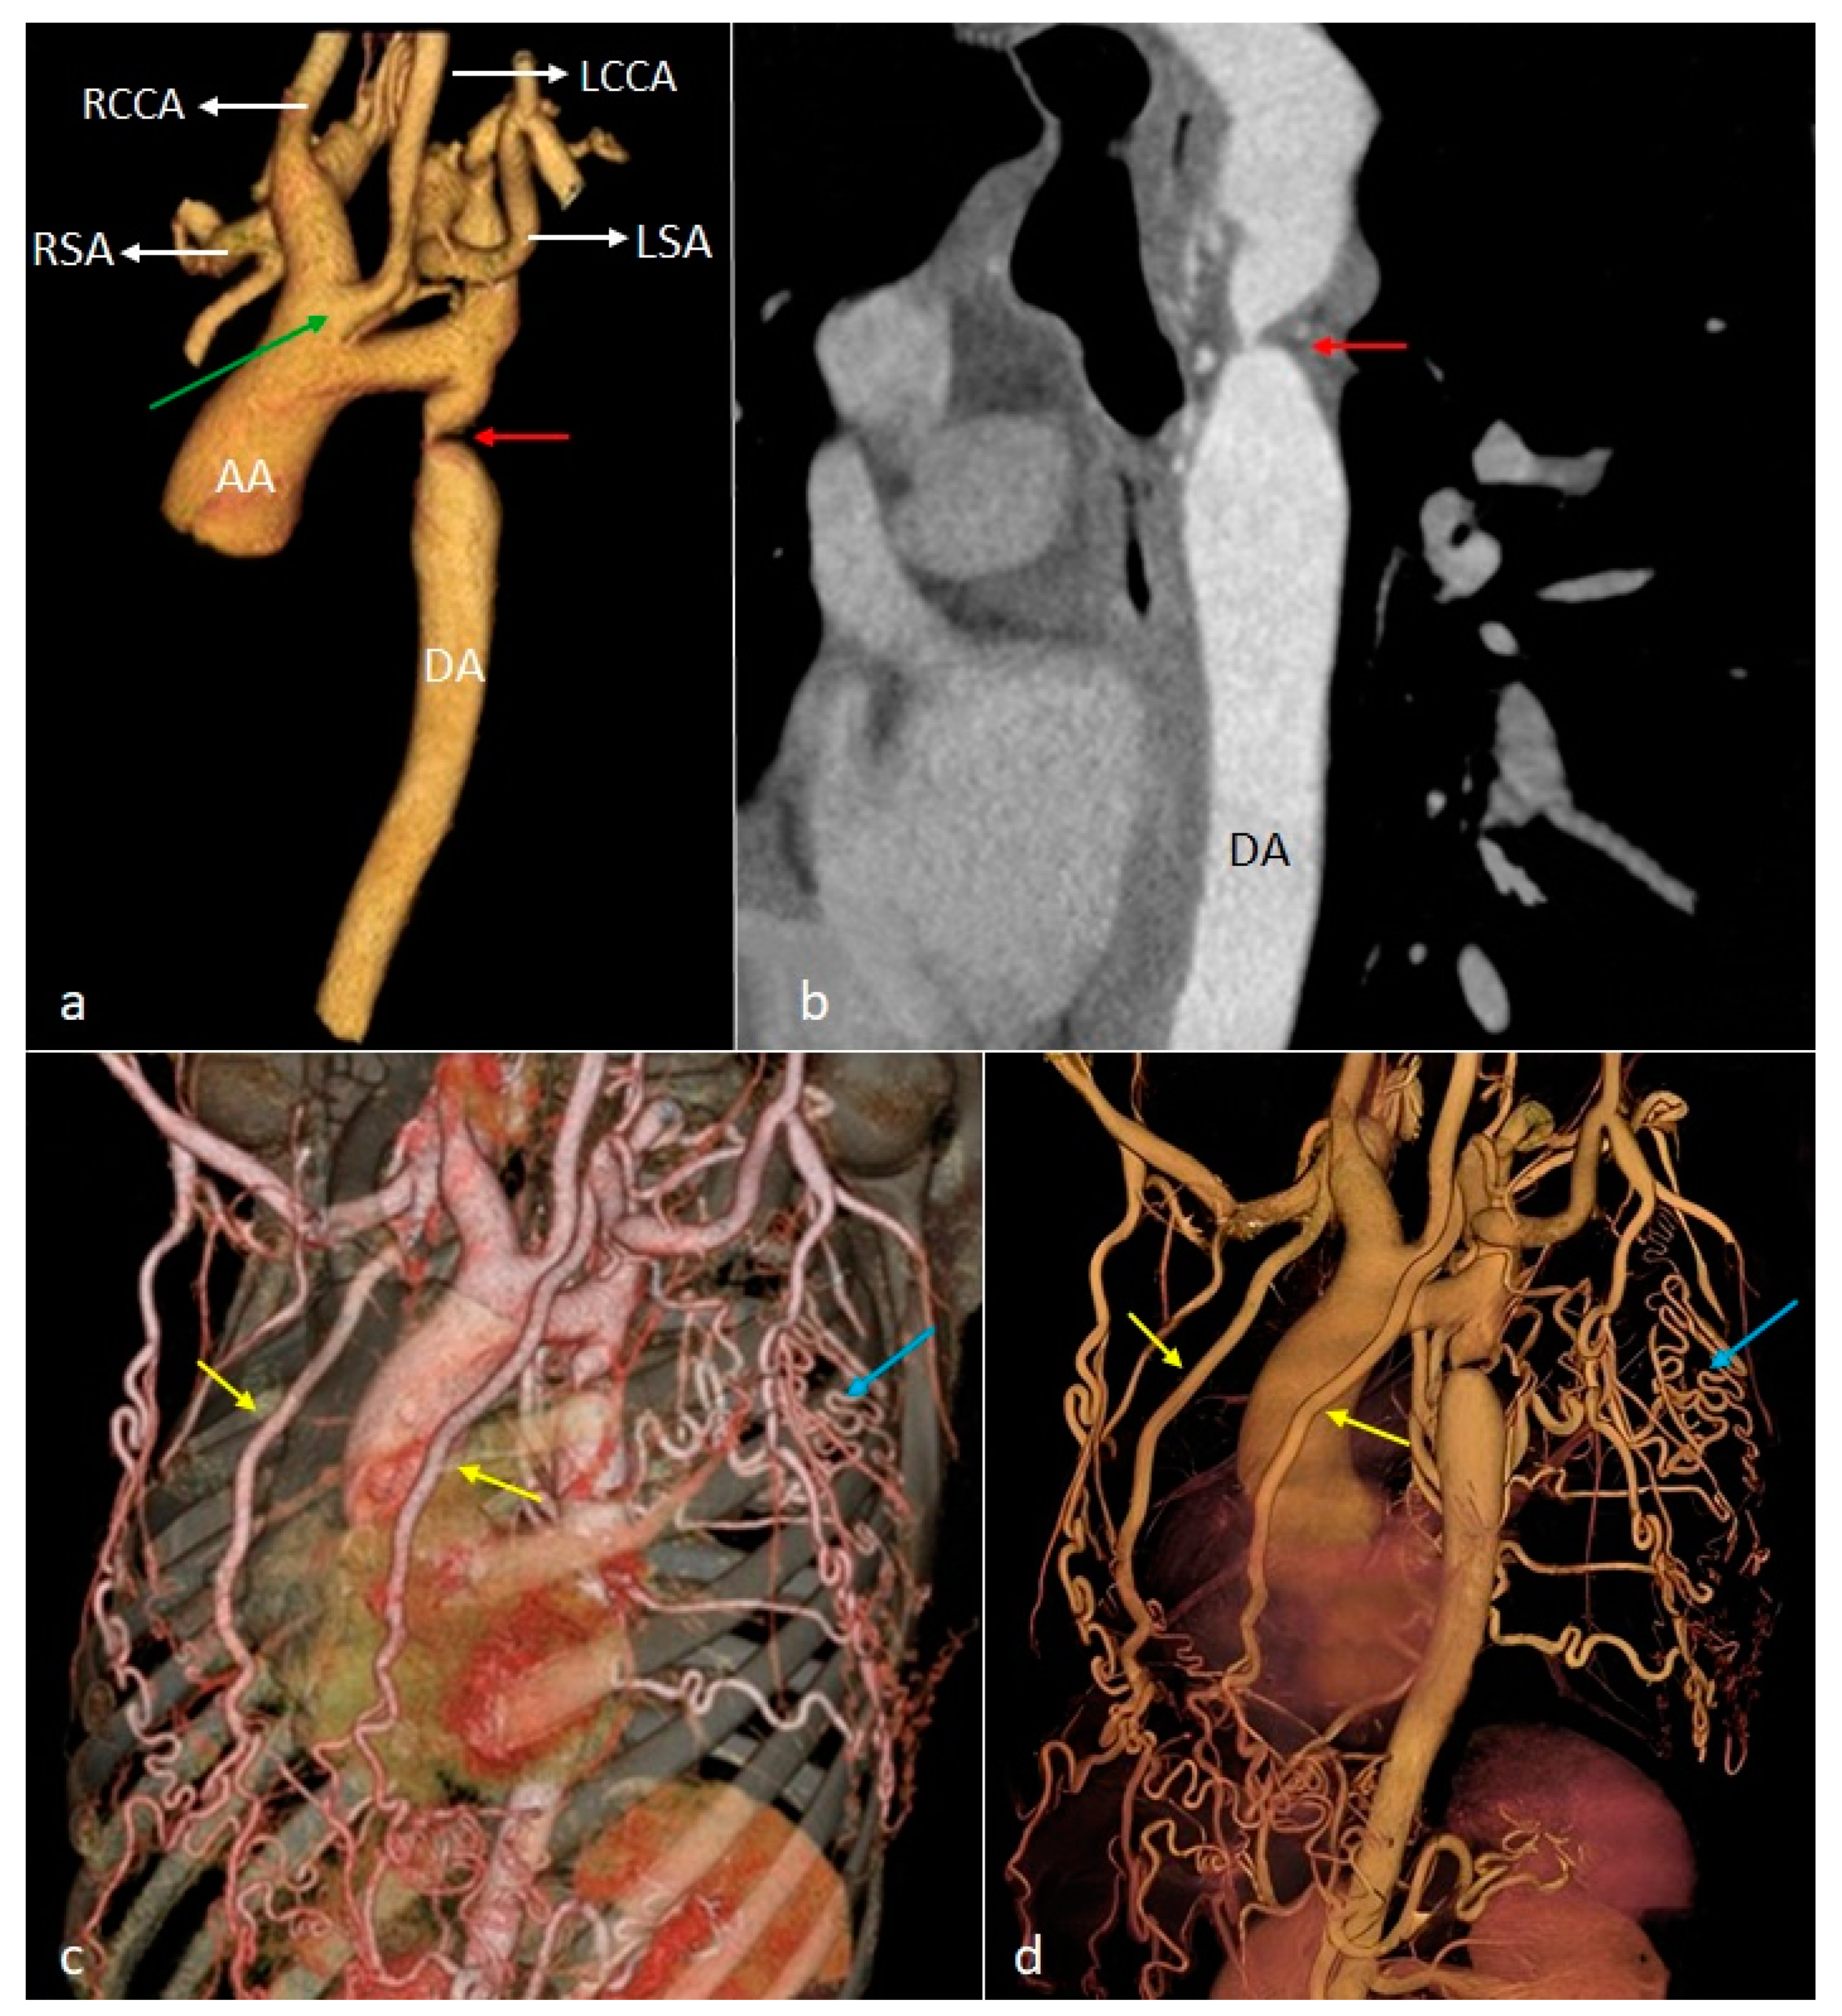

| AA | Ascending aorta |

| DA | Descending aorta |

| LCCA | Left common carotid artery |

| LSA | Left subclavian artery |

| RCCA | Right common carotid artery |

| RSA | Right subclavian artery |